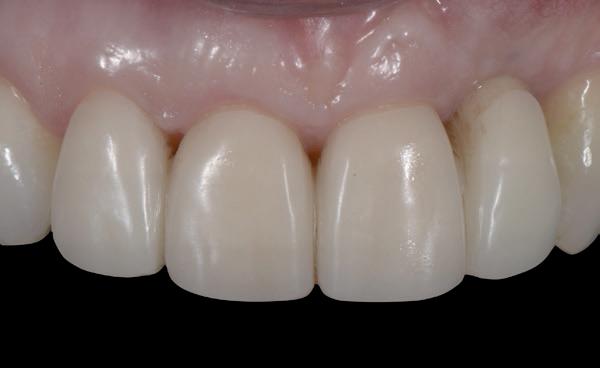

De flap en graft worden met poly-propelene 6.0 hechtingen gefixeerd. De tijdelijke reconstructie wordt herplaatst (foto 17-20).

Na 4-6 weken kan het aangebrachte healing abutment worden vervangen door een tijdelijk abutment. Deze wordt aan de kunststof reconstructie verbonden om zo de gingiva ter plaatse van de 22 te vormen. Zo lijkt het of er geen implantaat maar nog steeds een wortel aanwezig is, wat het esthetisch eindresultaat ten goede zal komen (foto 21-23). Vanaf 4-6 maanden ziet het weefsel er gezond uit. Nu kan met de uiteindelijke restauratiefase worden gestart (foto 24 en 25).

Bij de evaluatie van deze casus blijkt dat het herstellen van de processen alveolaris ter plaatse van de 22 is gerealiseerd en dat de gingiva qua positie en volume rond de 22 en 23 is verbeterd. Het implantaat is goed ge-osseointegreerd en de gingiva rond het implantaat heeft een natuurlijke vormgeving gekregen. De kronen zijn met moderne technologie en esthetisch hoogwaardig vervaardigd door het Oral Design Center Holland. Met dank aan Eric van der Winden.

De dentale mediaanlijn is rechtop gezet, maar staat niet helemaal gelijk met de faciale mediaan. Echter, mevrouw is functioneel en esthetisch naar tevredenheid afbehandeld (foto 27-30).